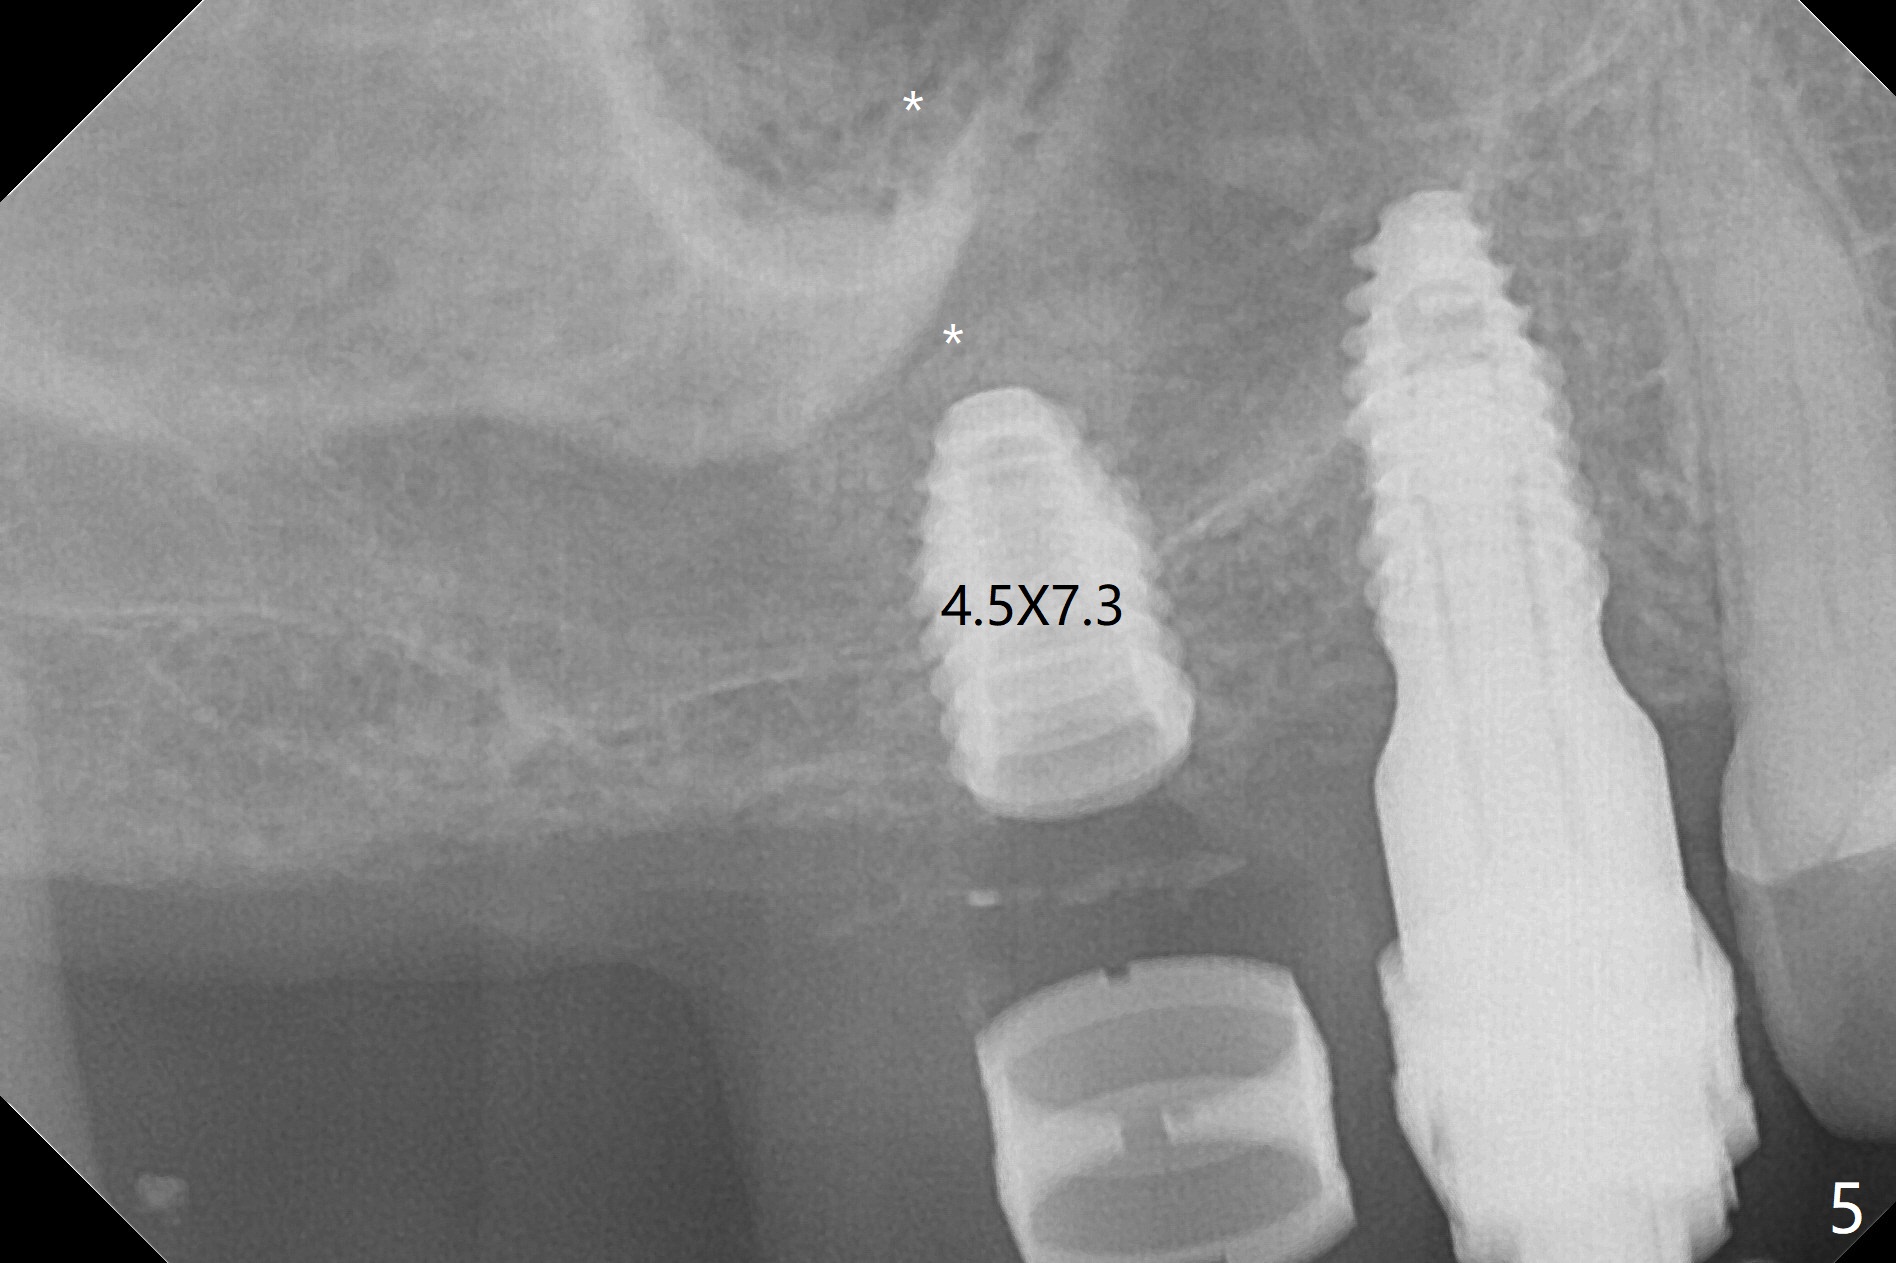

Osteotomy at #3 is performed last (Fig.1,2); as planned, a 4 mm cortical tap is used with guide for sinus lift. Unfortunately the sinus membrane is perforated. Implant placement is aborted. Instead Osteogen plug is inserted into the osteotomy, which is fixed in place by acrylic extending from the provisional at #4. Osteotomy for #3 implant will be attempted with control of the depth in 4 months. The patient has allergy to Amoxicillin (rash). When switching to Clindamycin, she develops diarrhea and loses 10 pounds. There is no abnormality at the site of #3 or 4 nearly 3 months postop (Fig.3). The next surgery will be most likely conducted without antibiotic 4 months postop. Try to draw blood for PRF. Take PA for #12 and 13 for possible impression. Remove the 3 temporary crowns, seat the guide across the arch and use no-stop fixture mounts at #4, and possibly 12 and 13. Follow the original drill sequence (check perforation after each drill, Fig.11) and use DIONavi sinus approach kit. Also load an appropriate stop for the round bur for sinus lift before hand. Mixture allograft with Metronidazole and PRF. In fact everything goes on as smoothly as planned. Osteotomy at #3 is underprep (3.5 mm in diameter drill instead of 4.0). The sinus floor appears to remain to be absent; 3.2 mm round bur is used for lift, alternating with water pumping. Following insertion of 3 pieces of PRF membranes and Vanilla Graft (Fig.4 *), a 4x10 mm dummy implant is placed. After additional bone graft (Fig.5 *), a final 4.5x7.3 mm implant is placed ~10 Ncm. The implant is placed deeper ~ 1 mm, followed by a 5.5x3 mm healing abutment (Fig.6). The implants at #12 and 13 seem to have osteointegrated (Fig.7). Impression is taken for #4, 12 and 13 with limited vertical space (Fig.8,9). An implant at #14 is being considered. There is faint bone graft around the apex of the implant 4 months postop (Fig.10). The implant sustains 25-30 Ncm torque when a 5.2x4(3) mm cemented abutment is placed. A permanent crown is cemented nearly 5 months postop (Fig.11). For the best cosmetic and masticating results, the occlusal surface should have certain degree of morphology, such as the buccal cusps (Fig.12 white curved lines). The abutment at #3 is placed and torqued to 30 Ncm before re-cementation of the repaired crown (increased occlusal surface contact). In fact the abutment at #4 is incompletely seated with a gap (Fig.13 <). The composite at #5 is dislodged while #3 crown is being repaired (*). The abutment at #4 is loose >1 year post cementation. The abutment remains incompletely seated (gap and longer apical space (double arrows)) when the abutment/crown complex rotates lingual mesiobuccal (Fig.14 curved arrow). Further proximal reduction and lingual rotation distobuccal leads to complete seating (Fig.15). It appears that incomplete seating at #13 is associated with hex mismatch (Fig.16, large apical space), which will be fixed next visit. One week later, the crown and abutment of #4 are seated together after crown repair (Fig.17). Since the abutment margin is subgingival, the crown is cemented, removed with abutment for residual cement removal and reseated with the abutment with torque at 30 Ncm. After this, the crown and abutment of #13 is reseated after mesiobuccal surface is trimmed (Fig.18), followed by pick up impression. A few days later, the crown/abutment are inserted together smoothly, the former cemented and the complex unscrewed for residual cement removal and last torqued at 30 Ncm without any X-ray confirmation.